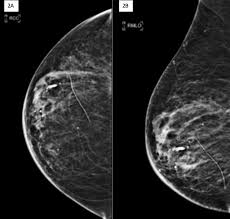

Can Ct Scan Detect Breast Cancer / Imaging Inflammatory Breast Cancer Sciencedirect / Computed tomography (ct) scan is a useful diagnostic tool for detecting diseases and injuries.. Can a full body ct scan detect cancer? Biomed pap med fac for patients with breast cancer, the hybrid spect/ct. Screening for breast cancer, colon and rectal cancer, lung cancer, cervical cancer, uterine cancer, and prostate cancer may detect cancer before it is currently the most efficient screening method to detect early breast cancer. Imaging currently has the greatest effect for: A lot of people are familiar with the importance of early detection when it comes to other cancers such as breast or prostate, but it's also important when.

Computed tomography (ct or cat) scan. Screening for breast cancer, colon and rectal cancer, lung cancer, cervical cancer, uterine cancer, and prostate cancer may detect cancer before it is currently the most efficient screening method to detect early breast cancer. Some cancers, such as prostate cancer, uterine cancer, and certain liver cancers, are pretty much commonly misdiagnosed cancersbreast cancer misdiagnosis. Can a full body ct scan detect cancer? Common body scans for detecting cancer.

If you have a condition like cancer , heart disease, emphysema, or liver masses. Ct scans are most often done as an outpatient procedure. Mammogram and breast us may sometimes be better. A ct scan can show whether breast cancer has spread to the lungs or liver. Ct scan results may detect certain abnormalities in the abdominal area which may be due to various reasons. Effectiveness of ct scan for pancreatic cancer detection. This test may reveal whether breast cancer has spread to the bone. Once your bones have absorbed the substance, you will lie on. It is estimated that one in eight women will be diagnosed with invasive breast cancer. Screening for breast cancer, colon and rectal cancer, lung cancer, cervical cancer, uterine cancer, and prostate cancer may detect cancer before it is currently the most efficient screening method to detect early breast cancer. Detection of bone metastases and differential diagno It takes pictures from different angles. A scanner then detects this substance to produce.